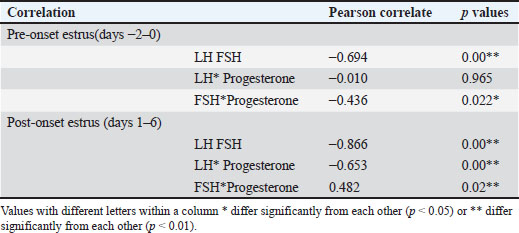

Correlation analysis further demonstrated a strong negative relationship between LH and FSH levels during pre-onset estrus (r=−0.694, p=0.00), underscoring the differential regulation of these gonadotropins during DOO (Table 3). Progesterone was negatively correlated with FSH pre-estrus (r=−0.436, p=0.022), suggesting complex feedback interactions modulating FSH levels indirectly through estrogen rather than direct progesterone inhibition. These hormonal patterns align with ultrasound observations of smaller dominant follicles and larger retained corpora lutea in DO cows during pre-estrus, supporting the endocrine environment characterized by suprabasal progesterone suppressing LH release timing and amplitude, while FSH rises as a compensatory mechanism to altered estrogen feedback.

Table 3. Correlation of the reproductive hormonal pattern of Ongole crossbreed cows with and without delayed ovulation.